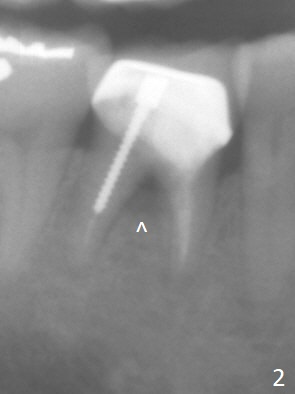

There appears no bone resorption at the septum of the tooth #30 of a 61-year-old man with 22 mm of bone (Fig.1; 10 years ago). The septum starts to have bone loss without symptom 3 years earlier (Fig.2 ^). Now the tooth is symptomatic with bone lesion also involving the mesial apex (Fig.3 *). Osteotomy will be initiated in the flattened septum with 4 mm mesiodistal width. Prior to placing a 13 mm IS implant, the depth of the last 2nd drill will be 15 mm. Prepare Magic Expanders. Place Magic Split blade buccolingually to expand the septum mesiodistally.